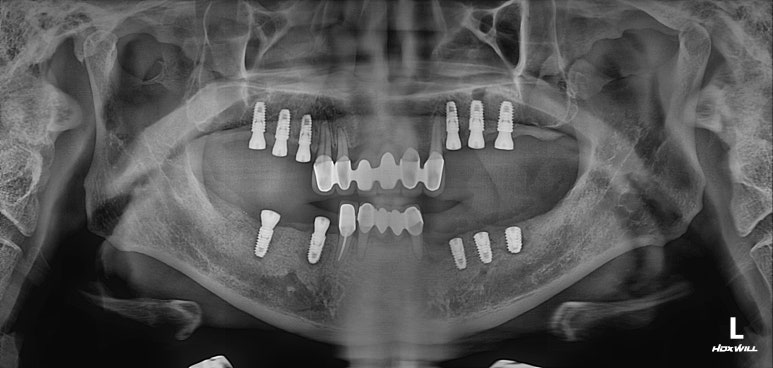

임플란트를 심고 3달이 지나면 2차 수술이 가능합니다.

이제 임플란트 머리 만들 준비를 해야죠~!

먼저 임플란트를 심었던 위턱 임플란트부터 임플란트 2차 수술을 시행합니다.

임플란트 2차 수술이란 잇몸에 묻혀있는 임플란트에 연결되어 있는 짧은 뚜껑 (coverscrew)을 제거하고, 긴 뚜껑 (healing abutment)을 연결하는 간단한 시술입니다.

비로소 임플란트 보철물을 연결할 수 있는 환경을 조성하고, 필요하면 잇몸 성형을 함께 시행해서 임플란트를 완성하고 나서 관리를 편하게 하실 수 있도록 만들어드리기도 합니다.

이렇게 오른쪽 아래부터 임플란트 2차 수술을 시행했습니다.

왼쪽 아래는 뼈이식을 많이했어서, 조금 더 기다리고 있는 모습입니다.

임플란트에 기둥 및 임시치아를 연결하고,

슬슬 씹는 연습을 시작하실 시간입니다.

보시면 임플란트가 더 길어진 것을 보실 수 있을거에요.

그리고 흐릿하게 뭔가 치아 형태의 외형을 가진 무언가가 보이시죠?

바로, 맞춤형 지대주 (custom abutment)와 임시치아 (temporary bridge)입니다.

너무 오랜만에 - 대략 반년 정도 흘렀지만, 실제론 그 전부터 잘 못씹으셨을테니.. 씹으시는 것이기에 연습을 조금씩 하시면서, 적절한 아래턱의 위치를 찾아가는 과정입니다.

앞니는 기존에 갖고 계셨던 도자기 재질의 크라운 색상이고,

어금니는 저희가 새로 만들어드린 임시치아의 색상입니다.

연습용으로 제가해드린 것이지만, 색상이 나쁘지 않답니다. ㅎㅎ

임시치아의 색상은 조금은 불투명하고 조금은 하얀 느낌이 진하지요.

그래도 적응이 빠르셔서, 2주만에 임시치아를 떼고 최종 임플란트 지르코니아 크라운 제작에 들어갔습니다!